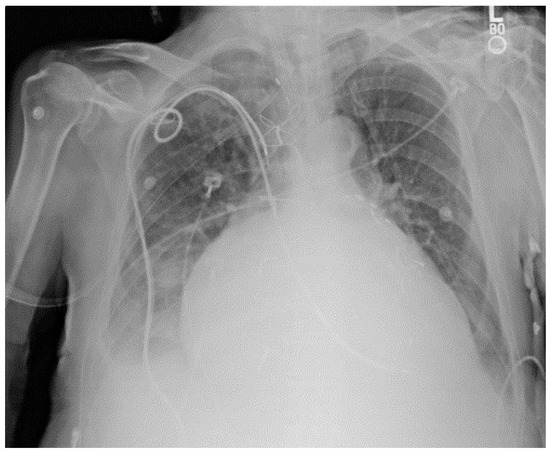

For traditional USM method, we have chosen different kernel size for Gaussian filter ( 15 × 15 , 19 × 19 , and 23 × 23 separately). Figure 3 shows a CXR from the portable CXRs database. The contrast of line structure in the spine and heart area is limited, and it is hard to find the tips of ET and NT. Enhancement is necessary for ICU CXR. Figure 4 shows the enhanced results obtained by using traditional USM. The EMEE value for the original image was 0.491. After enhancement, the EMEE values were improved to 0.841 (Figure 4c), 0.980 (Figure 4f), and 1.106 (Figure 4i), corresponding to the Gaussian kernel size of 15 × 15 , 19 × 19 , and 23 × 23 , respectively. Although, the EMEE values were improved, some important edge information still did not show clearly in the image, especially when the kernel size was smaller. When the kernel size of Gaussian increased, the noise and the edges were enhanced simultaneously. As a result, Figure 4c,f,i did not have high contrast, which was predictable based on the properties of the traditional USM algorithm.

Figure 3. An image from portable chest radiograph (CXRs) database.